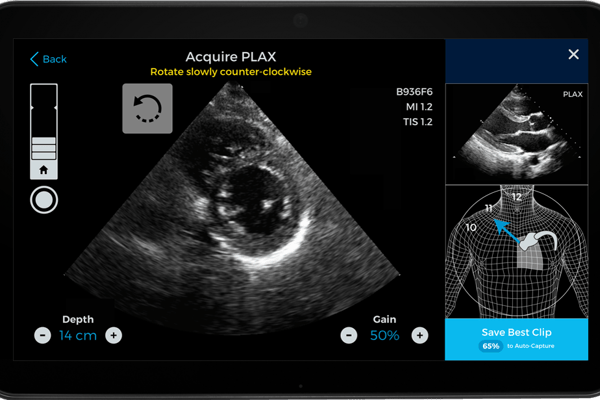

Caption Health fokussiert sich auf die Ultraschalluntersuchung des Herzens. Genauer gesagt darauf, diese so zu vereinfachen, dass sie besser eingesetzt werden kann und Spezialisten entlastet.

Die Echokardiographie ist eine der wichtigsten nichtinvasiven Untersuchungen des Herzens. Sie zeigt via Schallwellen die Beschaffenheit und Größe des Herzens an, gibt Aufschluss über seine Durchblutung und hilft so beim Erkennen von Herzmuskelentzündung, Herzrhythmusstörungen, Vorhofflimmern oder drohendem Herzinfarkt. Seit Mitte der Sechzigerjahre hat sie sich in deutschen Arztpraxen etabliert. Die Geräte sind über die Jahre besser geworden. Aber das richtige Anlegen des Ultraschallkopfes und die daraus resultierenden Bilder erfordern immer noch einige Expertise. „Wir haben uns vorgenommen, das drastisch zu vereinfachen, damit praktisch jeder nach kurzer Unterweisung damit zurechtkommt“, sagt Technologiechef Koepsell, der vor fünfzehn Jahren nach Kalifornien übersiedelte. Das Produkt des Duos ist eine Software, die nicht nur vorgibt, wo der Schallkopf je nach Körperbau des Patienten am Brustkorb angelegt werden muss, sondern dann auch die besten Aufnahmen empfiehlt.

Wie schnell die Software auf den Markt kommt, hängt nicht nur von der FDA, sondern auch den Anbietern von Ultraschallgeräten ab. Das US-Unternehmen Terason, ein Pionier bei portablen Ultraschallgeräten, hat man bereits als Partner gewonnen. Man erwartet die Zulassung in den USA Anfang nächsten Jahres, ein paar Monate später für Europa.